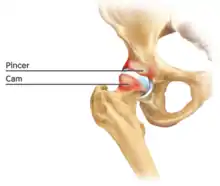

Cam-type femoroacetabular impingement

Cam impingement is created by the abnormal development of the femoral head-neck junction causing what has previously been described as a 'pistol-grip deformity'. This type of deformity is characterised by varying amounts of abnormal bone on the anterior and superior femoral neck at the head-neck junction (see fig. 6). The head-neck junction is at the base of the ball of the hip, where it joins the short neck, which in turn carries on downwards into the femur, or thighbone, itself. A bony protrusion or bump at the head-neck junction has been likened to a cam, an eccentric part of a rotating device. This leads to joint damage as a result of the non-spherical femoral head being forced into the acetabulum mainly with flexion and/or internal rotation. This may impart compression and shear forces to the articular cartilage, and may lead to labral tears and peeling away of the articular cartilage from the underlying bone, so-called cartilage delamination (see fig. 8).[9][10]

Standard arthroscopic treatment of symptomatic cam FAI involves debridement (resection) or repair of any labral [10] and chondral injuries [11] in the central compartment of the hip, and subsequent reshaping of the head-neck junction of the upper femur (osteochondroplasty) in the peripheral compartment [12][13] using high-speed motorised burrs that are similar in design to a dentist's drill (see fig. 9).